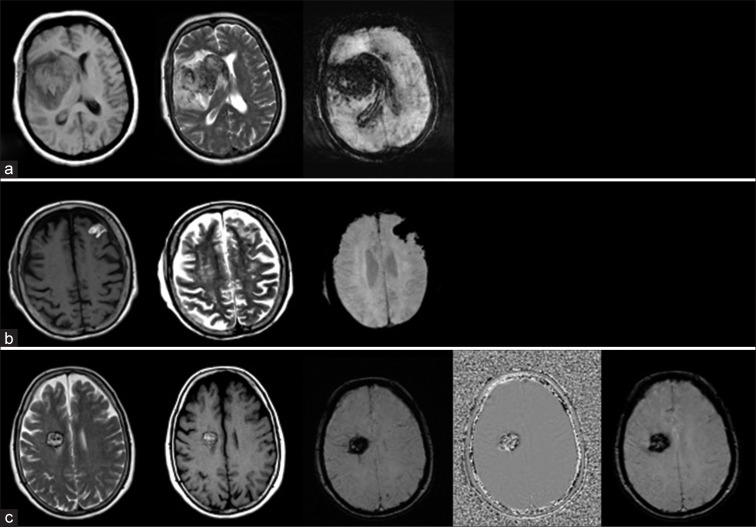

With advances in magnetic resonance imaging (MRI) sequences, there has been increased identification of microbleed/microhemorrhage across different population ages, but more commonly in the older age group. These are defined as focal areas of signal loss on gradient echo MRI sequences (T2* and susceptibility-weighted images), which are usually <5 mm in size representing hemosiderin deposition with wide ranges of etiologies. Susceptibility-weighted imaging (SWI) has become a routine MRI sequence for practices across the globe resulting in better identification of these entities. Over the past decade, there has been a better understanding of the clinical significance of microbleeds including their prognostic value in ischemic and hemorrhagic stroke. Cerebral amyloid angiopathy and hypertension are the two most common causes of microbleeds following peripheral and central pattern, respectively. In the younger age group, microbleeds are more common due to familial conditions or a wide range of hypercoagulable states. This review outlines the pathophysiology, prevalence, and clinical implications of cerebral microhemorrhage along with a brief discussion about the technical considerations of SWI.